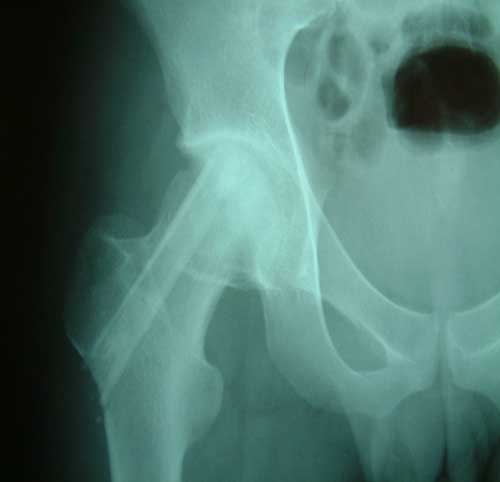

股骨头缺血性坏死MRI显示坏死区          微创手术方法,采用隧道减压刮除死骨